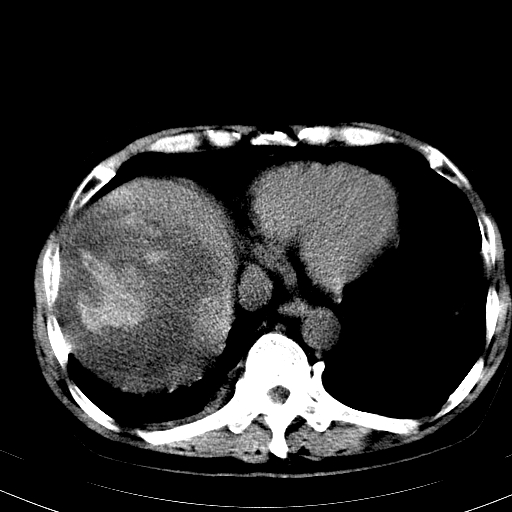

以下是引用卜一在2008-6-23 15:38:00的发言:[br]本例延时期的图象未扫完,单纯平扫 动脉期及门脉期特征分析:平扫低密度较大肿块,内见不规则出血灶,界限清楚。动脉期边缘结节样强化,门脉期病灶边缘进一步强化并范围明显缩小。因此考虑:血管瘤伴出血!